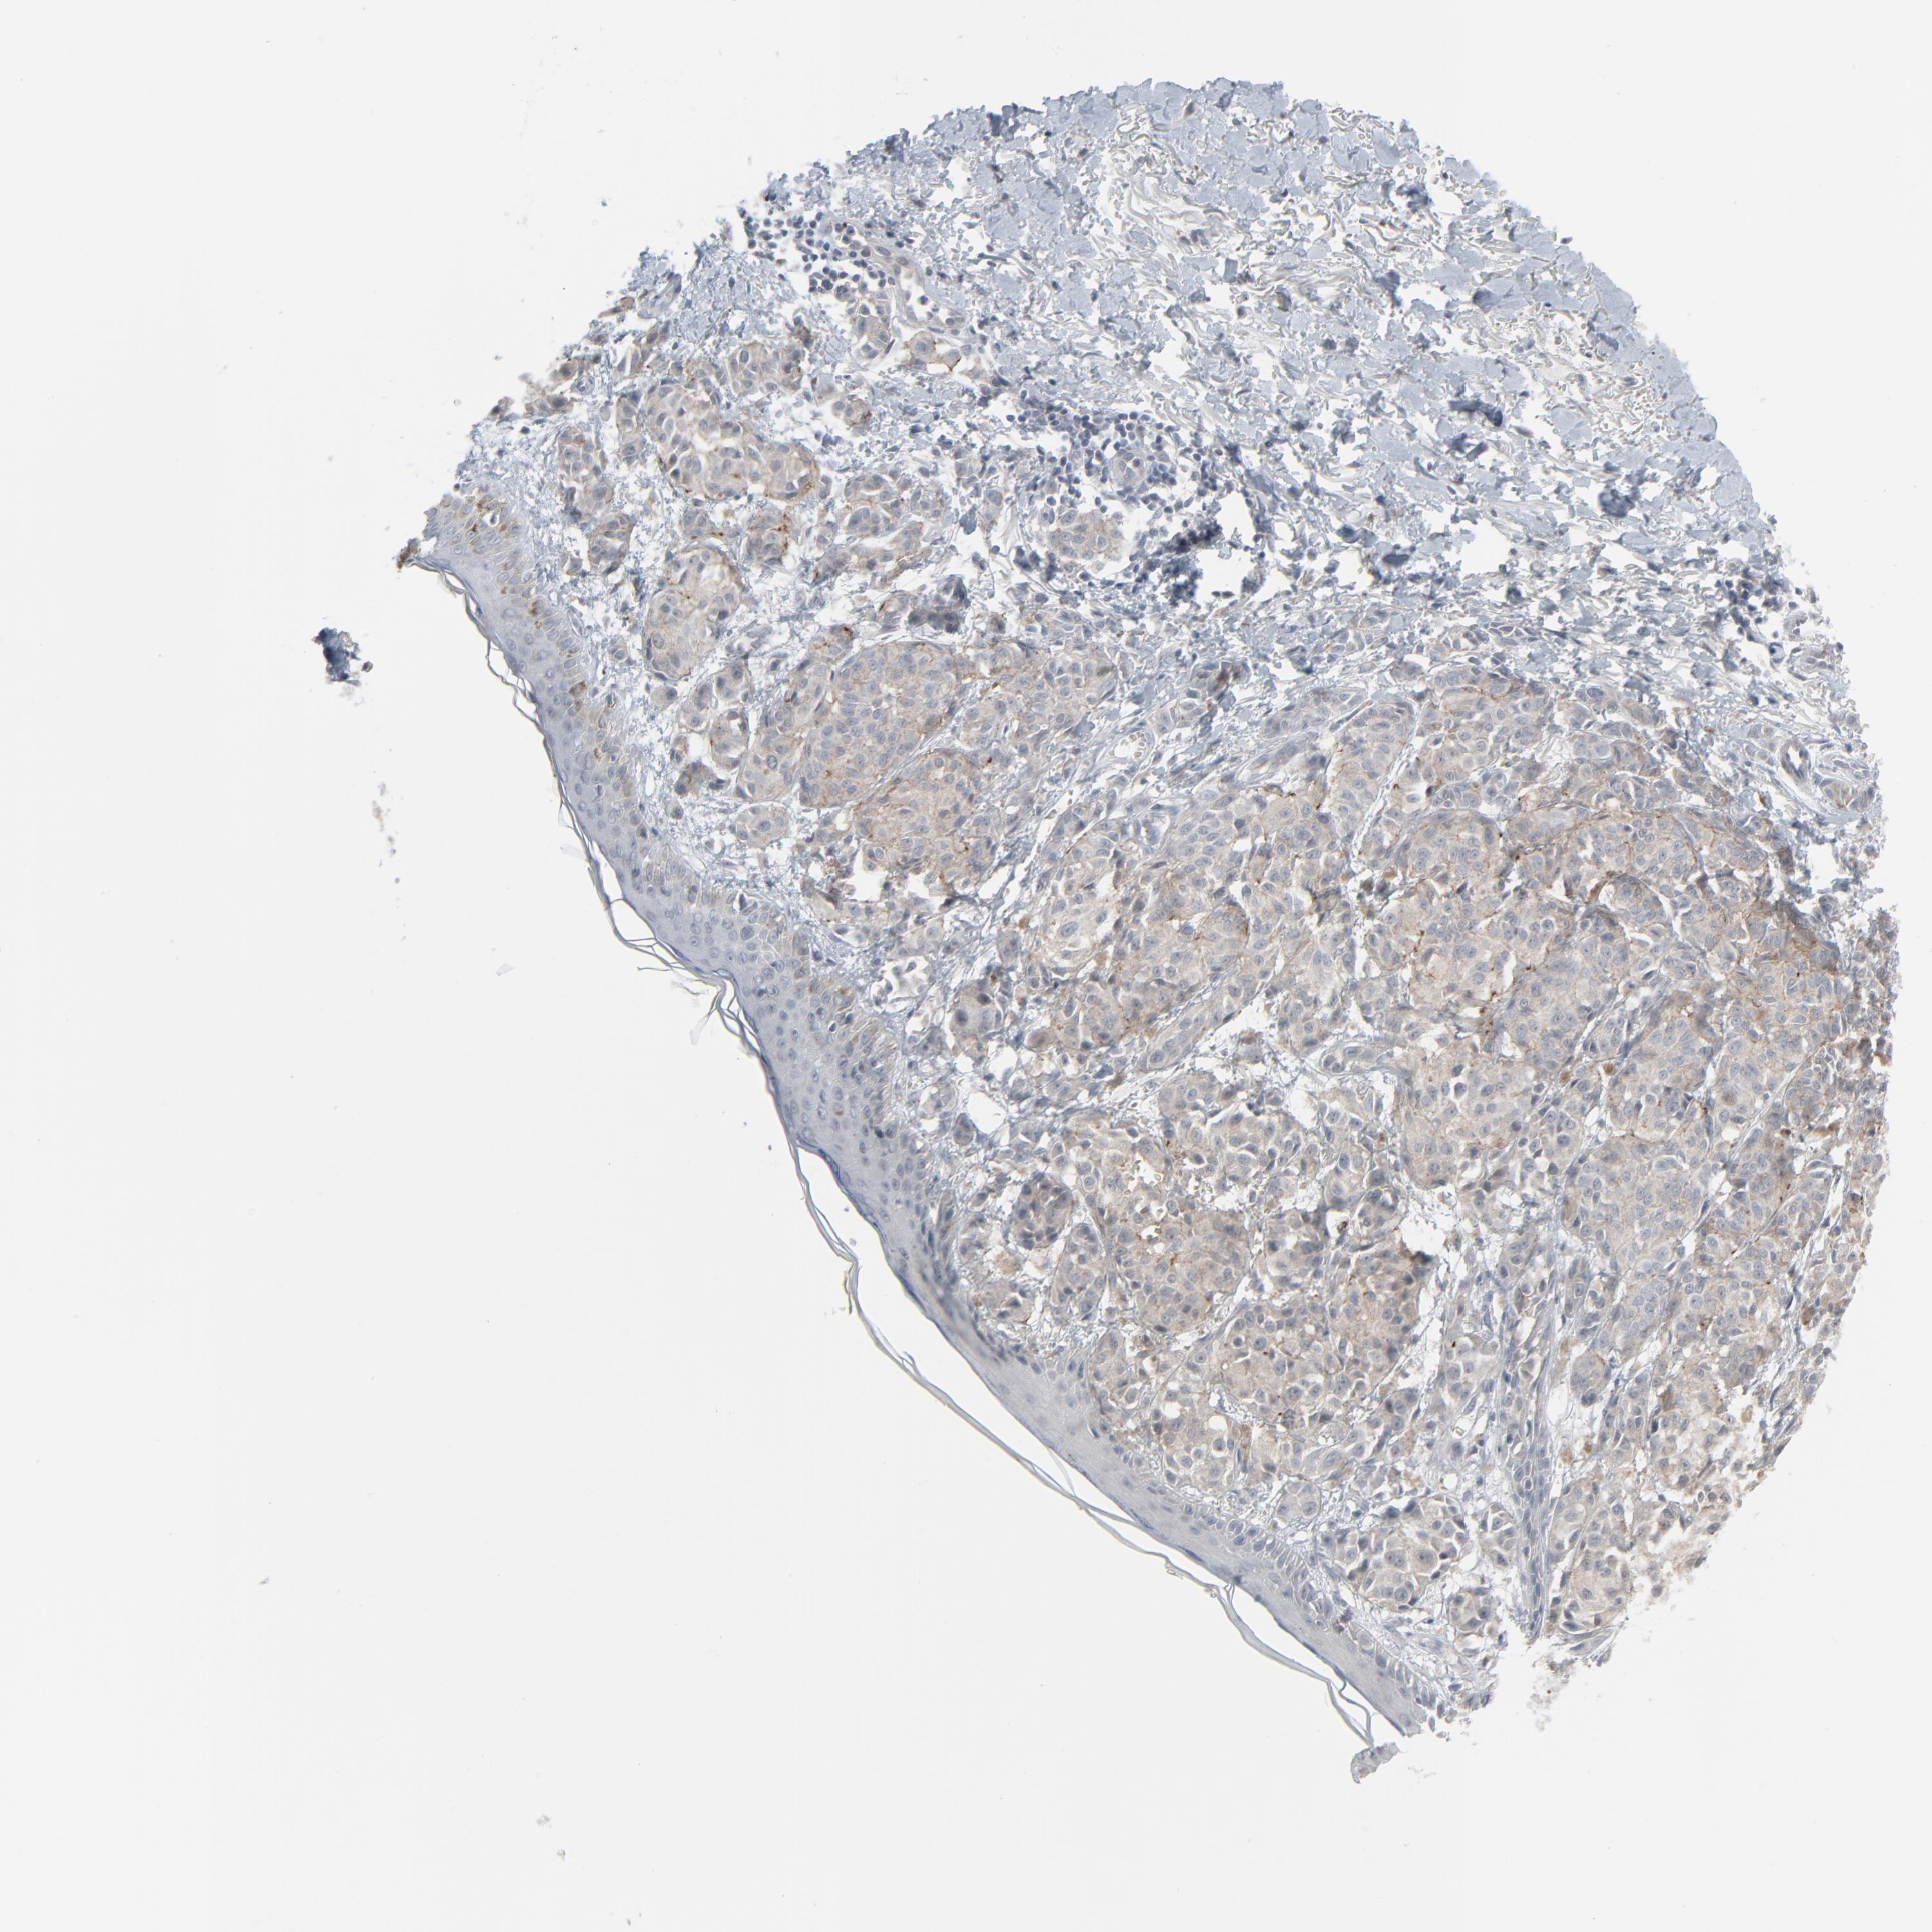

MELANOMA - Protein expressioni

A mouse-over function shows sample information and annotation data. Click on an image to view it in a full screen mode. Samples can be filtered based on level of antibody staining by selecting one or several of the following categories: high, medium, low and not detected. The assay and annotation is described here.

Note that samples used for immunohistochemistry by the Human Protein Atlas do not correspond to samples in the TCGA dataset.

Antibody stainingi

Antibody staining in the annotated cell types in the current human tissue is reported as not detected, low, medium, or high, based on conventional immunohistochemistry profiling in selected tissues. This score is based on the combination of the staining intensity and fraction of stained cells.

Each image is clickable and will lead to virtual microscopy that enables deeper exploration of all samples and also displays staining intensity scores, fraction scores and subcellular localization as well as patient and tissue information for each sample.

Antibody HPA003278

Antibody CAB022450

Staining

High

Medium

Low

Not detected

Intensity

Strong

Moderate

Weak

Negative

Quantity

>75%

75%-25%

<25%

None

Location

Nuclear

Cytoplasmic/membranous

Cytoplasmic/membranous,nuclear

Malignant melanoma, NOS

Malignant melanoma, Metastatic site